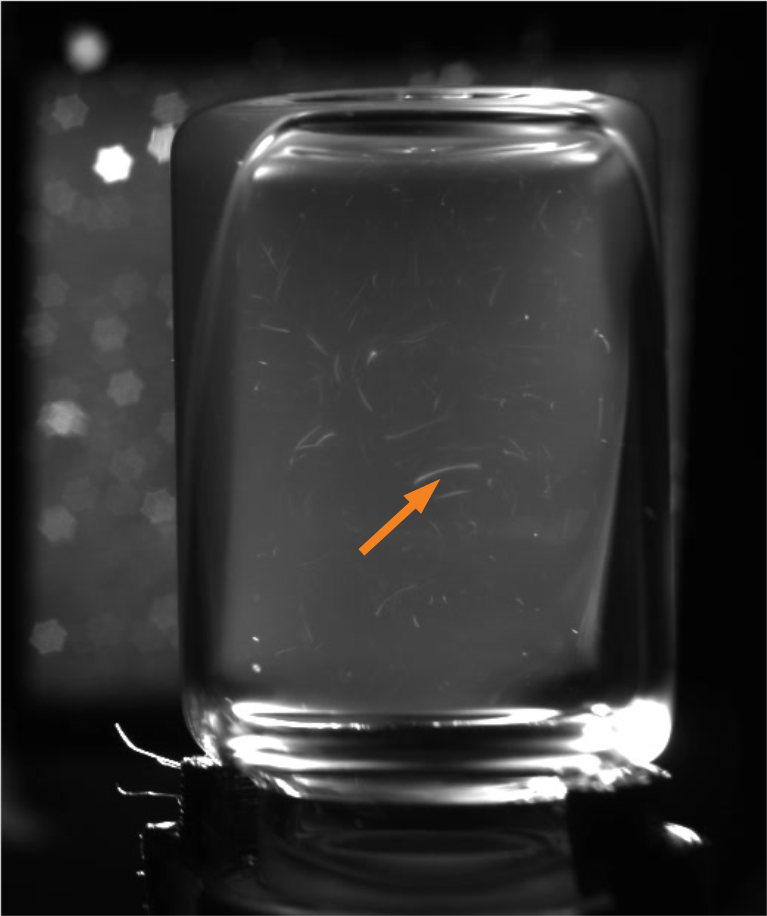

Correct lighting conditions are a prerequisite for identifying anomalies within liquid vaccines, since, due to a lack of contrast, their identification under natural lighting conditions is currently infeasible for human or automated visual inspection. A light intensity must be found that is sufficient for illuminating the vial while providing a moving contrast to identify the smallest particles [20]. To obtain a moving contrast human inspectors shake the vials to induce a swirl during manual inspections. Automated approaches meanwhile, such as the semi-automatic Seidenader V90+ inspection machine, use servo motors to stir up particles inside the vials. However, this approach has a side-effect of creating bubbles within the liquid. Furthermore, light reflections and dust particles resting on the outer surface of the vials can often be mistaken for anomalies within the liquid [20]. Opaque suspensions further increase the task difficulty by obscuring anomalies, which as a result are frequently only briefly visible. Figure 1 depicts some of these challenges.

Motion Blur: One of the challenges regarding tuning the camera prior to recording the vials, was to find a depth of field that provides a sharp focus for all the particles within the suspensions. This means that the aperture size has to be narrowed to enable a sufficiently deep depth of field. A smaller aperture requires longer shutter speeds in order for sufficient light to reach the camera’s sensor. Despite increasing the light emitted by our strobe to the maximum setting, we are only able to record using 25 fps, and as a result the initial 20 – 40 frames from each recording suffer from motion blur (Examples are provided in Figure 3). Therefore, due to particles’ increased velocity after the vial is rotated using the motor, even good particles appear elongated during the initial frames of each recording.